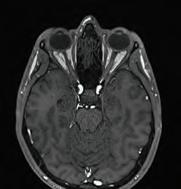

MRI IN PEDIATRIC ECMO PATIENTS

The world’s first study of children receiving extracorporeal membrane oxygenation (ECMO) therapy using mobile magnetic resonance imaging (MRI) has been conducted.

ECMO involves oxygenating the blood outside the body and is available at eight UK centres. Patients who require ECMO therapy beyond a standard ventilator are critically ill.

Reasons may include lung failure, heart failure or infection.

A total of 25 children were scanned in the mobile MRI. It was used for routine examinations and for further diagnosis of abnormalities.

To evaluate the image quality of the mobile low-field MRI, a comparison image was taken in a permanently installed normal-field MRI for each of the children examined.

“We were more than satisfied with the results. Although the image quality of the mobile MRI is not as highresolution as that of a fixed device, the image data are ideal for emergency diagnostics and, above all, can be retrieved immediately,” said Hemmen Sabir, Leader of Neonatal Neurosciences at University Hospitals Bonn. bit.ly/3zzOse2